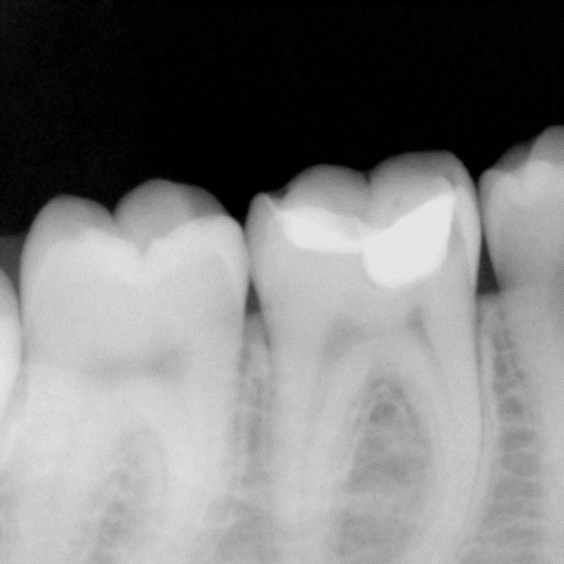

A female patient presented with sensitivity and occasional pain on stimulus in her lower left back tooth. On clinical examination deep carious lesion was present in her lower left first molar tooth (Fig.1). Tooth was non tender to percussion. Radiographic examination revealed deep lesion in close proximity to the pulp with no significant periapical changes (Fig. 2). Patient had a high caries index and therefore a bioactive restoration with Predicta Bulk was considered.

Fig. 2. Radiographic examination